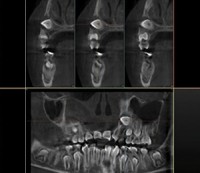

Panoramic

The detailed panoramic image to visualize clearly all oral anatomical structures through programs suitable for adults and children.